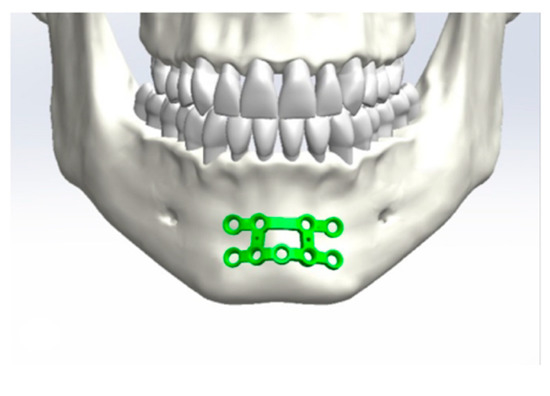

2.1. Design of the Plates

Application of the Plates